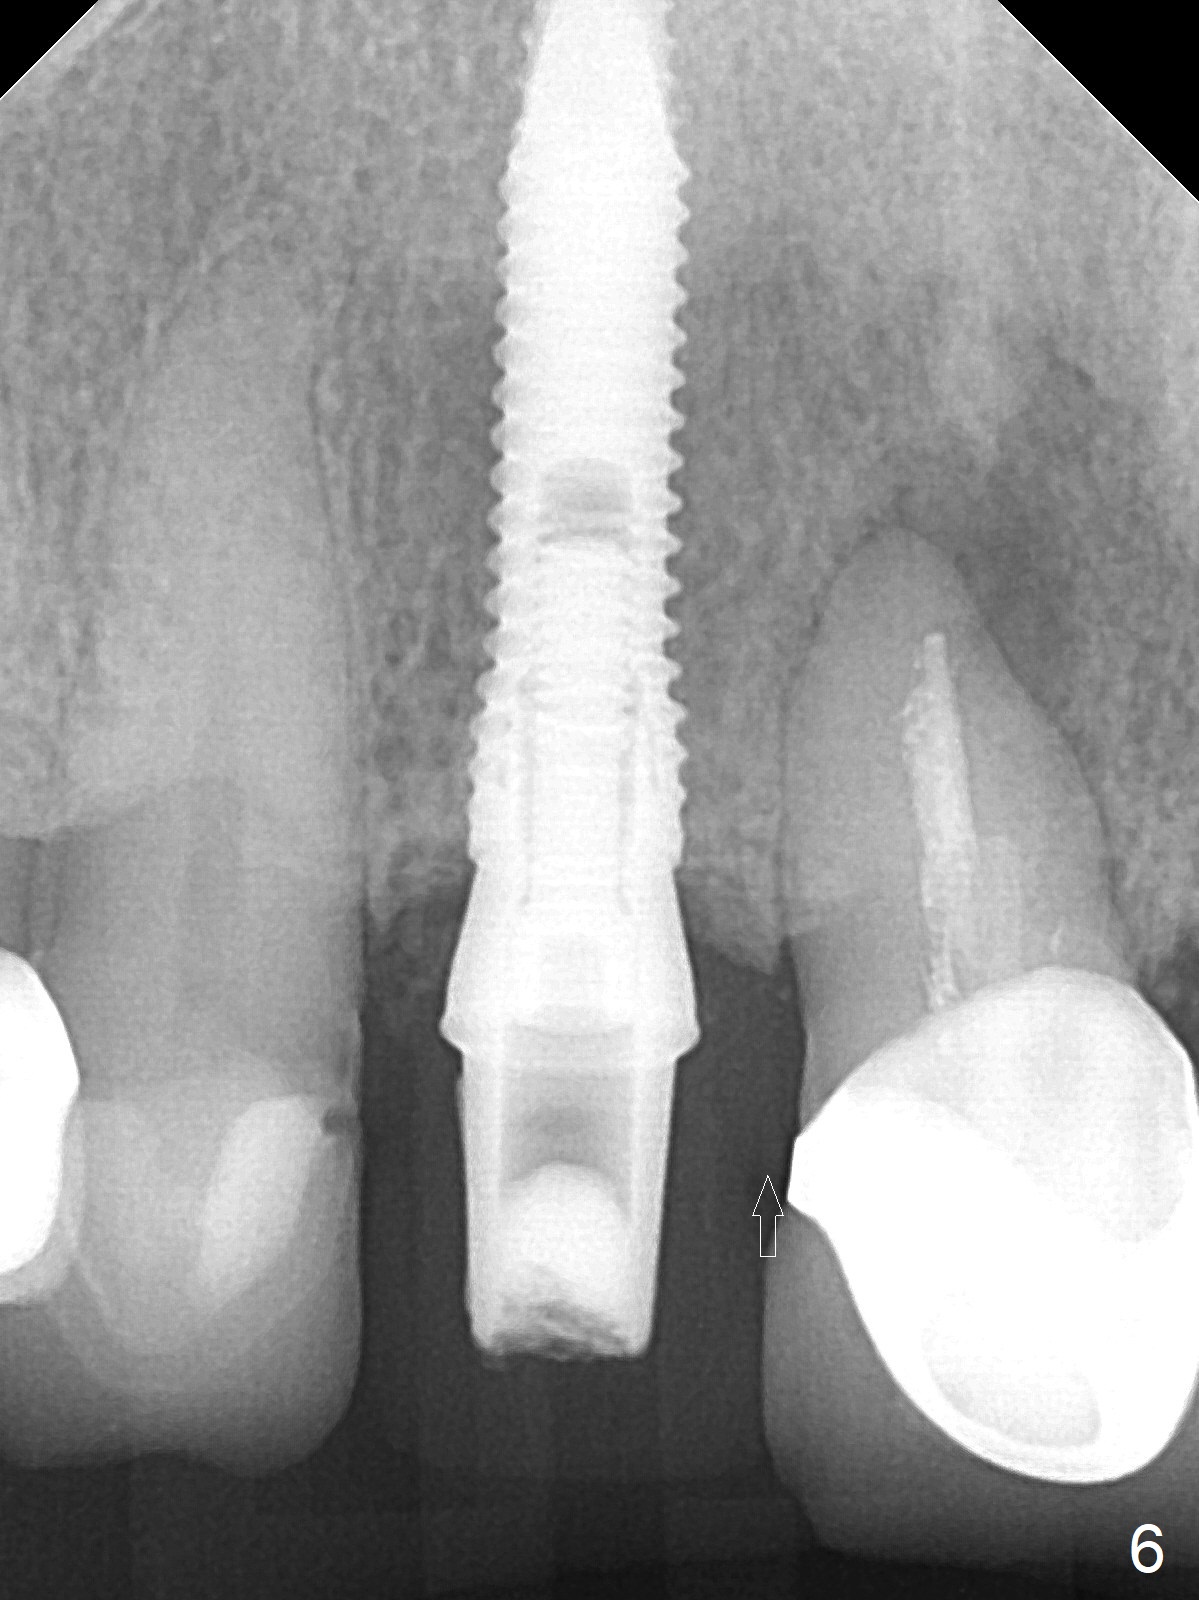

In fact the residual root (Fig.3) is easy to remove. A 3.8x16 mm implant is placed (Fig.4 (with 2 mm buccal gap)) at the level as planned (Fig.2). Insertion torque is acceptable. After placing a 4.5x5(3) mm gold-coated abutment and allograft (Fig.5), an immediate provisional is fabricated (the existing crown is lost). The patient is pleased with the quick, painless procedure.

She returns for impression 4 months postop; the abutment margin is substantially subgingival (Fig.6 arrow). The abutment is changed to 4.5x4(4) mm one before impression. There is no bone resorption 9 months post cementation (Fig.7).